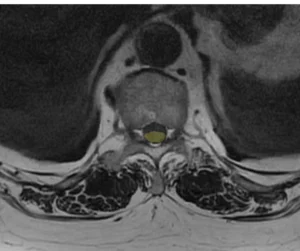

Проведённая МРТ грудного отдела позвоночника выявила две интрадуральные экстрамедуллярные опухоли, вызывающие критическую компрессию спинного мозга. Эти образования были диагностированы за 2–3 года до обращения. Однако, пациентка отказывалась от операции из-за страха, возраста и избыточного веса.

Учитывая возраст пациентки, общую соматическую нагрузку, прогрессирующую неврологическую симптоматику и необходимость срочно устранить компрессию спинного мозга, было принято решение о симультанном (одновременном) удалении обеих опухолей. Это решение позволило сократить время нахождения пациентки под наркозом и минимизировать риски. В таких случаях, когда дорога каждая минута, на помощь приходит спинальная хирургия с использованием современных технологий.

Операция была выполнена двумя командами нейрохирургов онкологов, работающих синхронно через разные хирургические доступы. Мы применили микрохирургическую технику, интраоперационный нейромониторинг и современное анестезиологическое обеспечение. Эти технологии позволили провести вмешательство максимально безопасно, сократить его длительность и уменьшить общую нагрузку на организм пациентки.